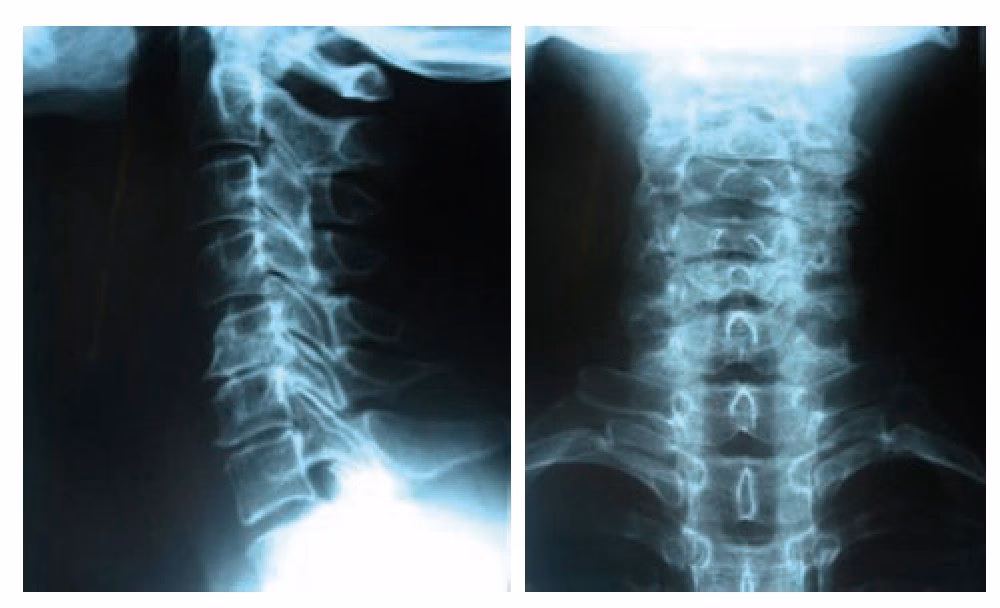

La lordosis cervical se refiere a la curvatura natural de la columna vertebral en la región del cuello, que normalmente se curva hacia adentro, en forma de C. Una lordosis 'normal' es esencial para la biomecánica adecuada del cuello y la cabeza. Sin embargo, problemas como la pérdida de la lordosis (rectificación o incluso cifosis cervical) o una lordosis excesiva (hiperlordosis) pueden ser fuentes significativas de dolor y disfunción.

La pérdida de la lordosis cervical, en particular, ha sido objeto de estudio. Se ha asociado con la disminución de la hemodinámica de la arteria vertebral, que son vasos sanguíneos importantes que irrigan el cerebro. Una investigación en particular evaluó los cambios en el flujo sanguíneo cerebral en pacientes con pérdida de lordosis antes y después de una corrección de la curvatura. Aunque se necesitan más estudios para confirmar estos hallazgos y comprender sus implicaciones clínicas, los resultados preliminares sugieren que la corrección de la lordosis cervical podría estar asociada con un aumento inmediato en el flujo sanguíneo cerebral. Esto subraya la importancia de la curvatura cervical adecuada no solo para la función mecánica del cuello sino potencialmente para la salud neurológica general.

Para cumplir los requisitos de este listado, tu documentación médica debe ser detallada e incluir evidencia de un examen exhaustivo de tu columna, el rango de movimiento de tu cuello, hallazgos de laboratorio e imágenes médicas (como radiografías, resonancias magnéticas o tomografías computarizadas) que muestren la anomalía específica. Dado que el dolor es difícil de medir objetivamente, la evidencia debe apuntar a una fuente clara del dolor.

- Resultados de pruebas de laboratorio y diagnóstico por imágenes (Rayos X, resonancia magnética, tomografía computarizada).

Necesitarás pruebas de imagen como radiografías, resonancias magnéticas y tomografías computarizadas que muestren la estructura de tu columna cervical. También son cruciales los informes médicos detallados, notas de progreso de tu médico, resultados de exámenes neurológicos o físicos, y un historial completo de tratamientos y tu respuesta a ellos.